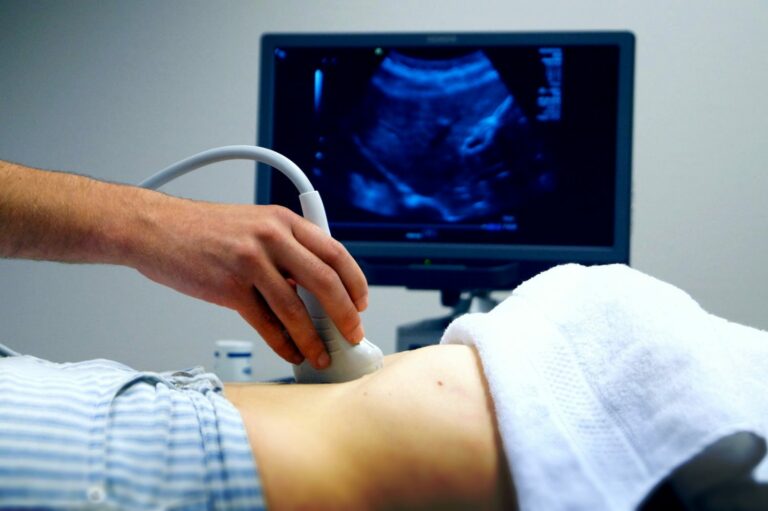

पाल्पा, भदौ १५ । गाउँमा भिडियो एक्सरे सेवा नहुँदा पाल्पाको निस्दी गाउँपालिकाका गर्भवतीलाई सदरमुकाम तानसेन तथा रामपुर धाउनुपर्थ्यो । उनीहरुलाई भिडियो एक्सरे सेवा लिन एक दिन पुरै बिताउनुपर्थ्यो । अब भने यहाँका गर्भवतीलाई सो सेवाका लागि अन्यत्र जाने समस्या टरेको छ ।

पालिकाले गर्भवतीलाई लक्षित गरी निःशुल्क ग्रामीण भिडियो एक्सरे सेवा सञ्चालन गरेको छ । पालिकाका सातवटै वडामा रहेका स्वास्थ्य चौकीमार्फत प्रत्येक महिना एक दिन सेवा दिन थालिएको स्वास्थ्य शाखा संयोजक रेमबहादुर दिसाले जानकारी दिए ।

वडा नं १ को बाकामलाङ स्वास्थ्य चौकीमा हरेक महिनाको २३ गते, वडा नं २ को सहलकोट स्वास्थ्य चौकीमा २२ गते, वडा नं ३ को झिरुवास स्वास्थ्य चौकीमा २१ गते, वडा नं ४ को मित्याल स्वास्थ्य चौकीमा ११ गते, वडा नं ५ को गल्धा स्वास्थ्य चौकीमा १४ गते, वडा नं ६ को अर्चले स्वास्थ्य चौकीमा १२ गते तथा वडा नं ७ को ज्यामिरे स्वास्थ्य चौकीमा १३ गते भिडियो एक्सरे सेवा दिइने उनले बताए । यही भदौ ११ गतेदेखि उक्त सेवा सुरु गरिएको हो ।

“प्रदेश सरकारले एक जना तालिम प्राप्त अनमीको व्यवस्था गरेपछि यो सेवा सुरु गरेका हौँ”, संयोजक दिसाले भे । गर्भवतीको समस्यालाई ध्यानमा राख्दै पालिकाले उक्त सेवा सुरु गरेको हो । गर्भवतीलाई वडामा रहेका स्वास्थ्य संस्थामार्फत हरेक महिना प्रत्येक वडा वडामा समय तय गरेर सेवा प्रवाह गर्न थालिएको उनले बताए । गाउँकै स्वास्थ्य चौकीबाट सेवा पाउँदा उनीहरुलाई ठूलो राहत मिलेको छ । यसअघि तानसेन र रामपुर धाउँदा यातायात, बास बस्ने लगायत समस्या थियो ।

स्थानीय स्तरमै सेवा पाउँदा सास्ती भोग्नुपर्ने समस्या टरेको निस्दी–४ की हिराकुमारी खाम्चाले बताइन् । “टाढा जानुपर्ने झन्झटले गर्भवती स्वास्थ्य परीक्षण गर्दैनथे, अब ठूलो राहत पुगेको छ”, उनले भनिन् । मेसिन बिग्रिने, स्वास्थ्यकर्मी अभावलगायत समस्याले कतिपय बेला भने सेवा सेवा नलिइकन फर्कनुपर्ने समस्या थियो । निजी क्लिनिकमा महँगीका कारण सेवा लिन समस्या थियो ।